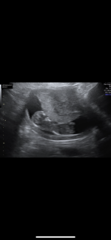

As an example these are my ultrasound direct scan pics from 12+6

Private Scan- Clinic Recommendations